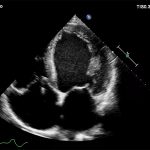

Imagini clinice:

Aplicatii: